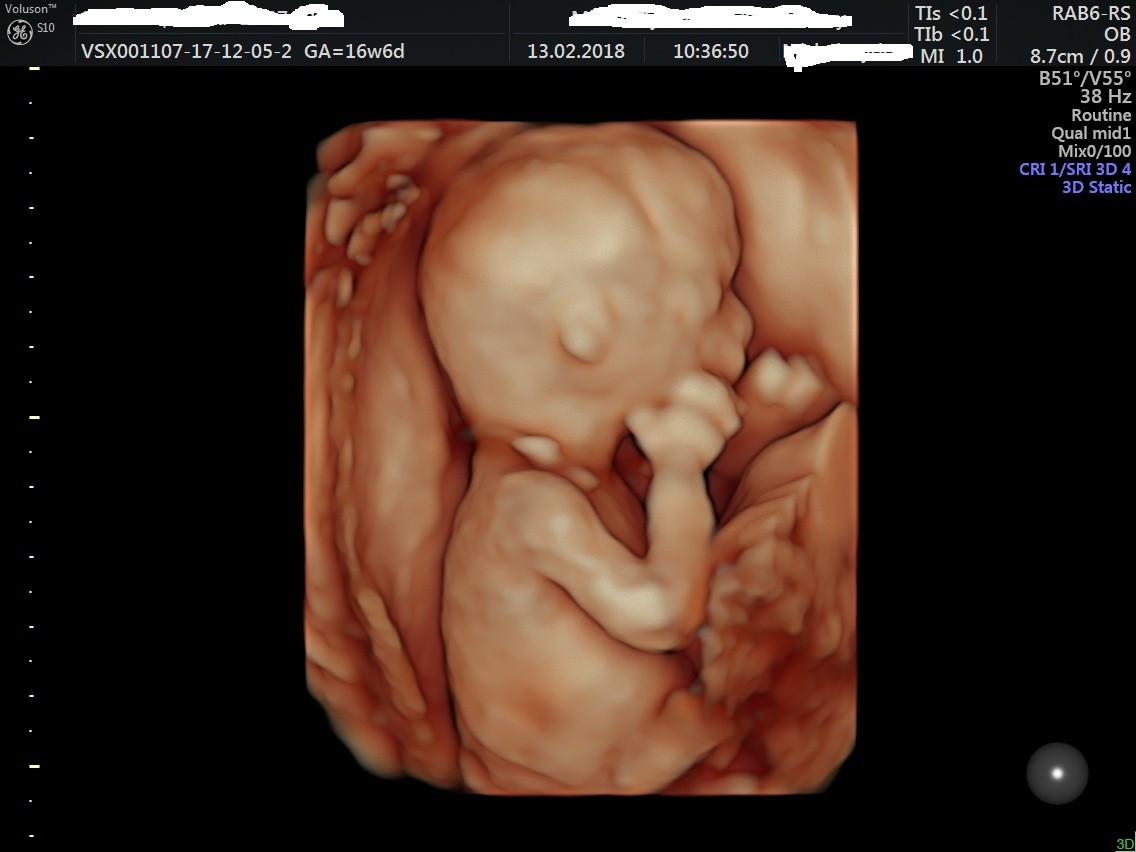

A to moj Synus :

(owiniety pepowina z przodu).